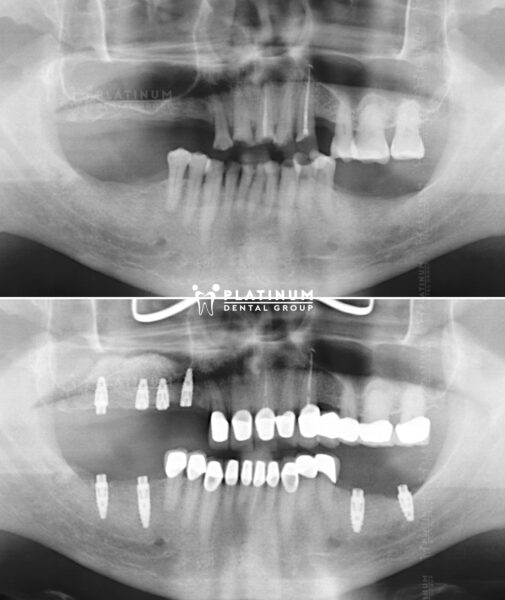

Nụ cười tươi trẻ của Mr. Dean Salonga thực hiện Implant All-On-4 tại Platinum Dental.